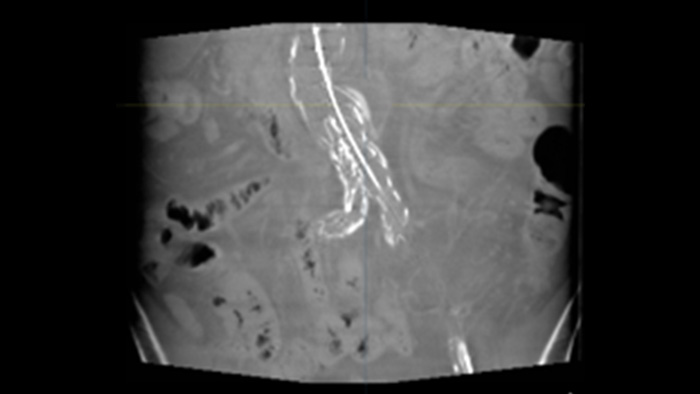

SmartCT Soft Tissue is an X-ray acquisition technique that generates a CT-like visualization of soft tissue in relation to other structures during procedures – all controlled via the touch screen at the table. You can use the CT-like images to assess soft tissue, bone structure and stent deployment.